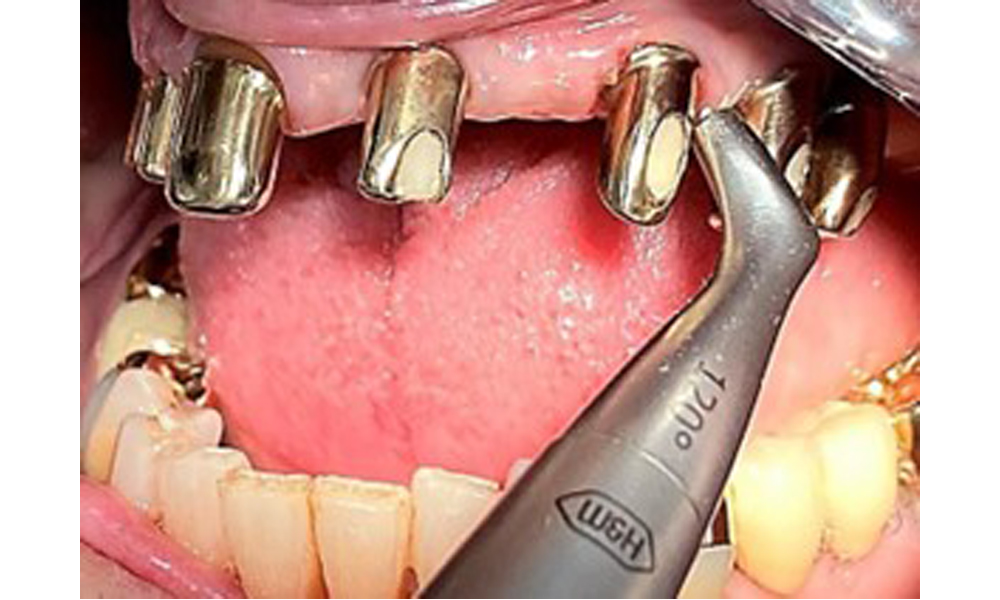

The patient was fitted with a combined removable maxillary telescopic prosthesis more than 25 years ago (Fig. 1, Fig. 2, Fig. 3) and is very happy with her dentures. The patient has an adequate fixed denture for the mandible (Fig. 4).

The dental findings are as follows: Combined removable implant and tooth-supported telescopic prostheses on implants 15, 13, 21, 23, 24, 25 and tooth 11 (Fig. 1, Fig. 2, Fig. 3). The patient was fitted with a fixed mandibular denture. Adequate bridges were present over 37 to 34 and 45 to 47 (Fig. 4), the crown margins were intact and there were no active caries. A composite filling with a marginal gap was present on tooth 43. There was mandibular gingival recession, exposing 1 to 3 mm of root surface. This also applies to 11.

Sonic/ultrasonic, or conventional manual instruments may be used to remove calculus and concretions present on the natural teeth (8). Titanium or plastic curettes (Fig. 10), or a plastic or PEEK attachment (Fig. 11) during ultrasonic treatment, should be used to remove mineralized plaque from implants to avoid damaging the implant surfaces.